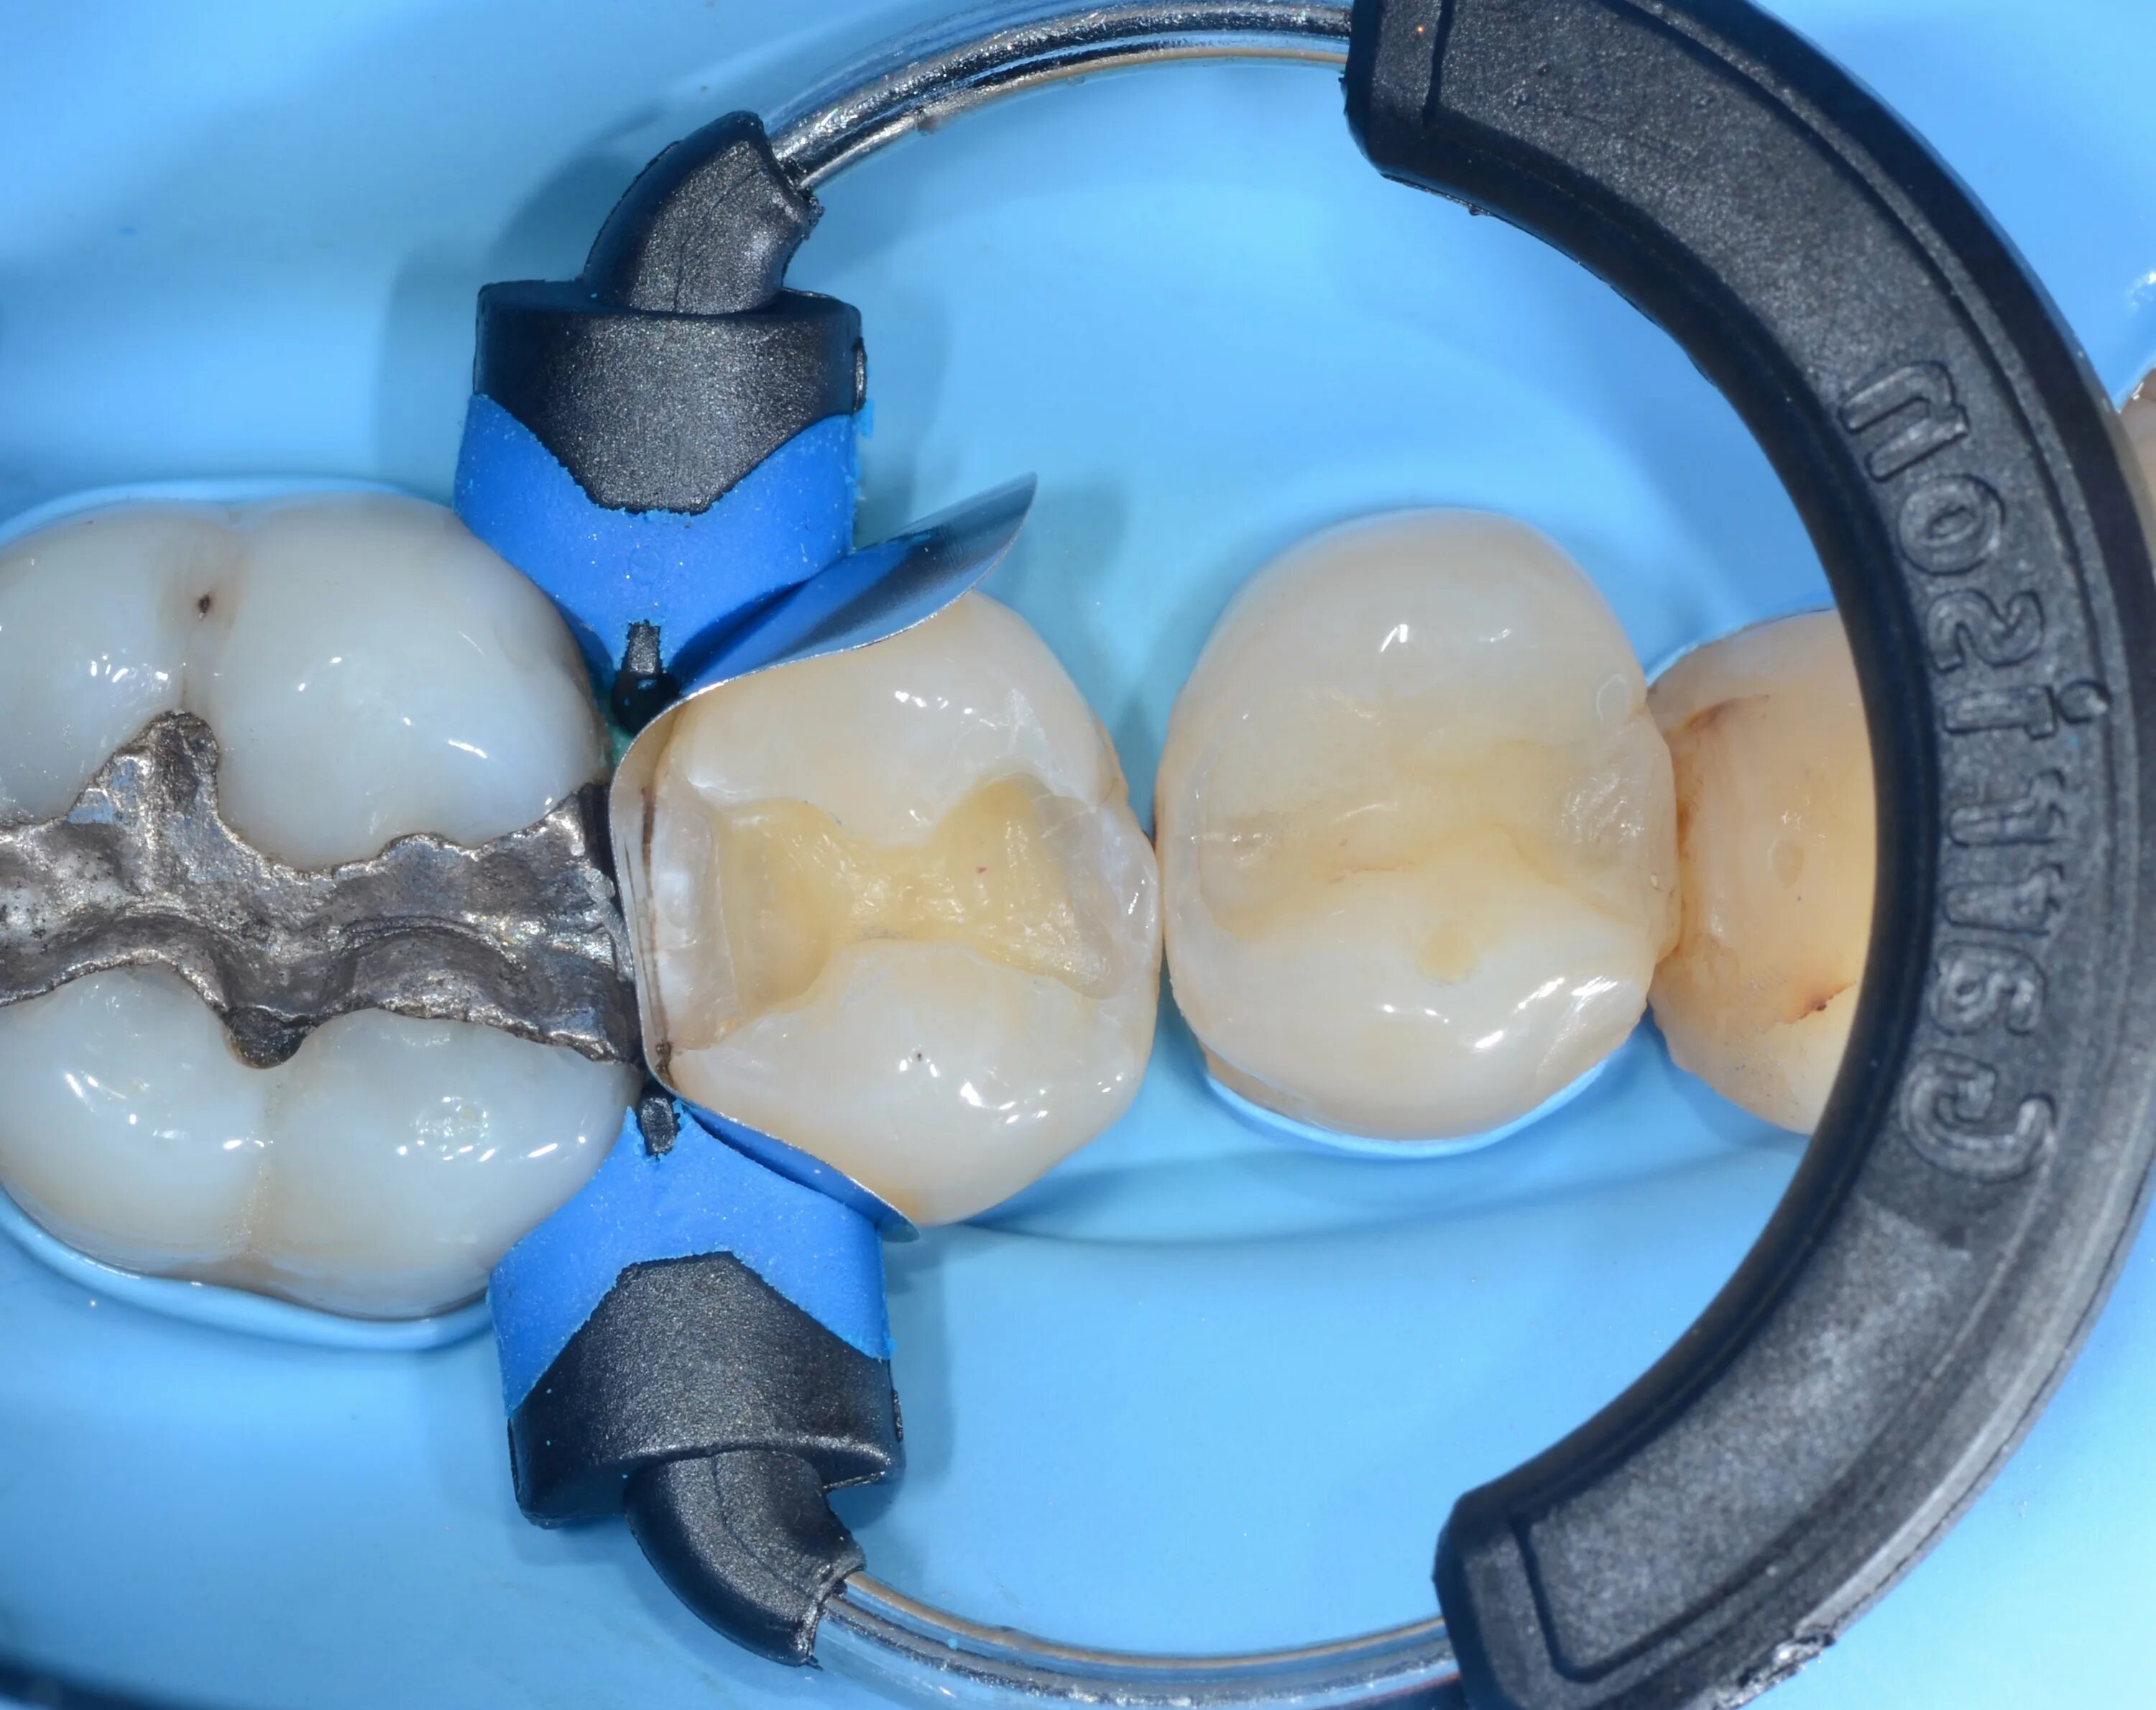

Матрица гаряева зубы и десна